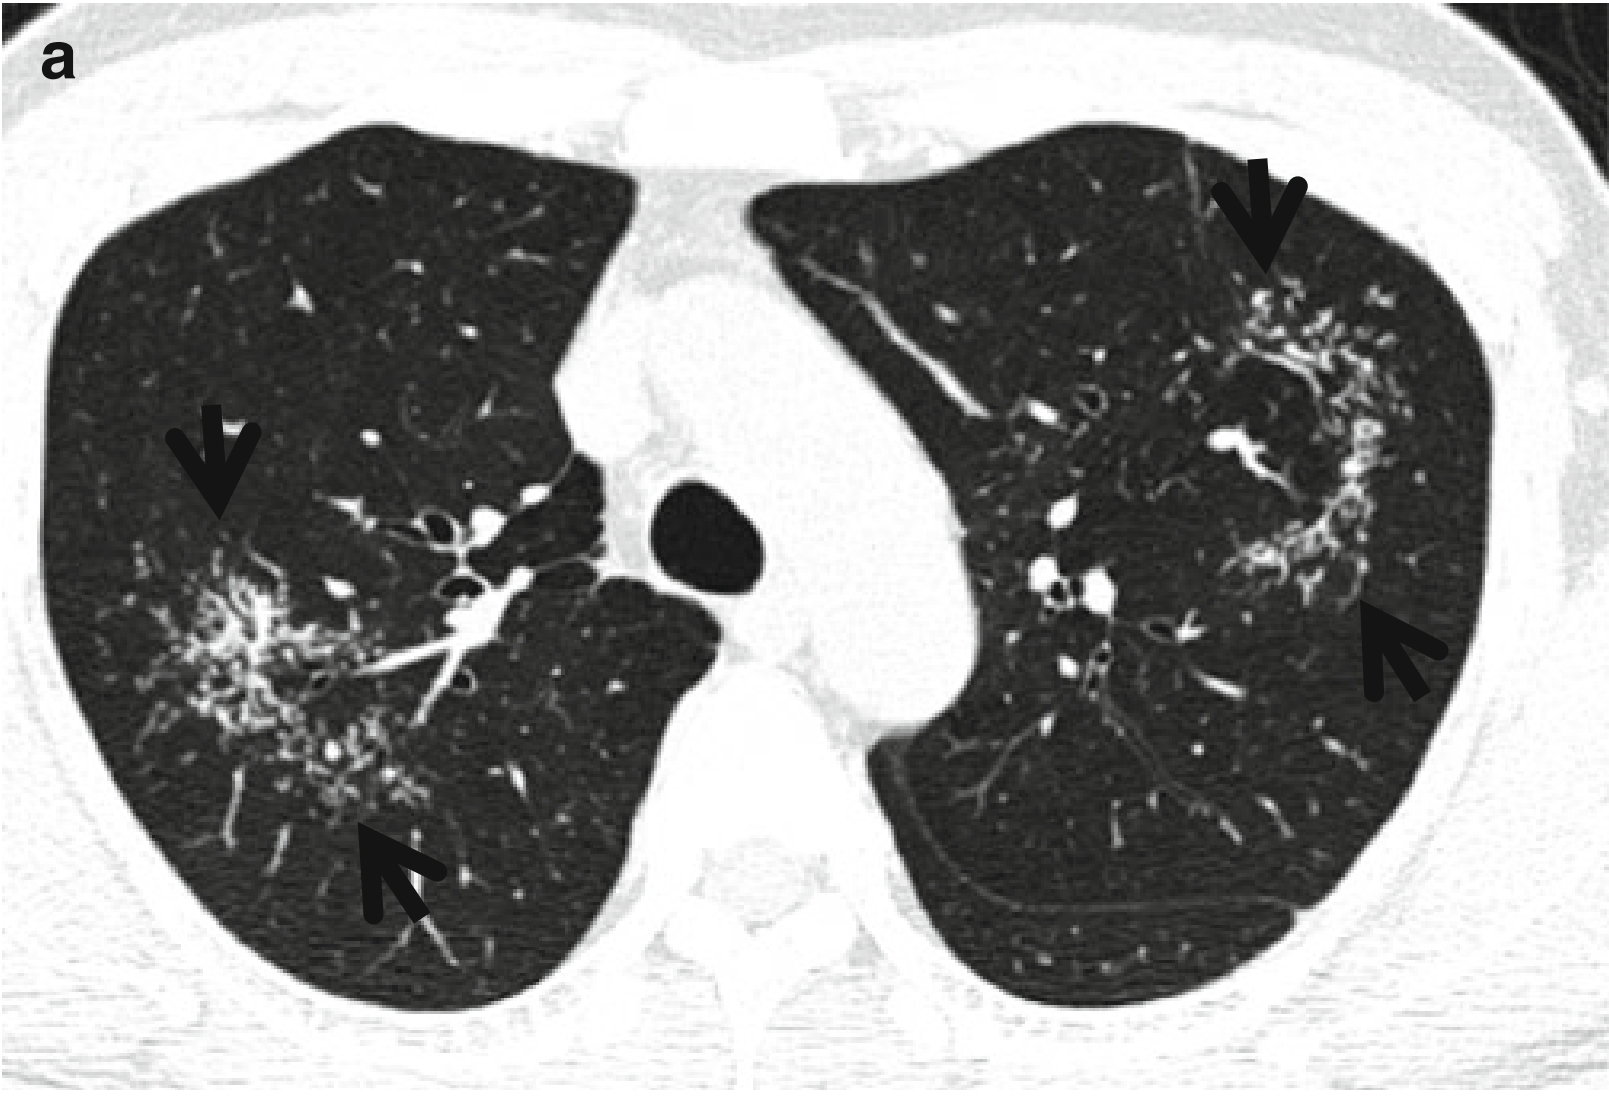

图2 CT星系征。

患者男性,44 岁,活动性肺结核。

(a.b)连续CT扫描(层厚=5.0 mm,低剂量模式)于右中间段支气管水平,可见左肺上叶上舌段CT星系征(箭头所示)。在层厚相对较厚的CT图像上。需要注意的是,不能把星系征看成磨玻璃密度影而诊断为浸润性肺腺癌。

(c)左肺上叶外科活检大体病理标本;可见多发结节状小肉芽肿相互聚集(箭头所示)。

(d)低倍光镜(×4)下可见:细支气管周围间质内见聚集的多发肉芽肿结节、其中心可见坏死。肉芽肿向心性汇聚,外围较分散。Br.细支气管。